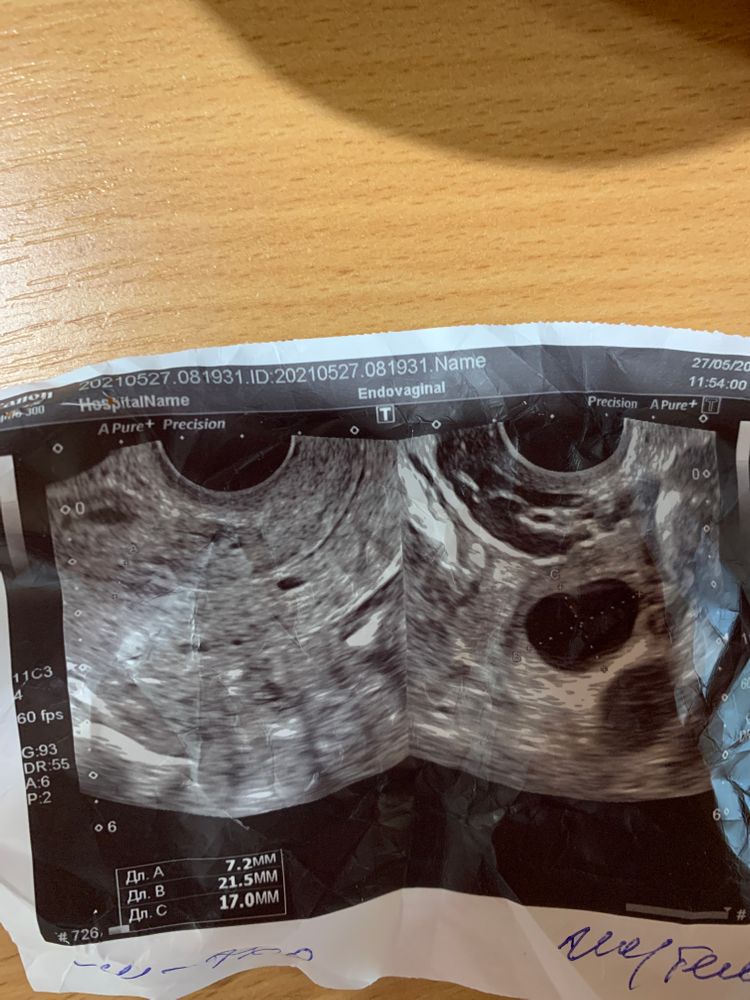

12 ДЦ и желтое тело

Всем доброго дня! Девочки, нужен ваш совет!Сегодня 12 дц, пошла на фоликулометрию с расчетом поймать О. Доктор сообщил, что овуляция уже была, желтое тело 21х17 мм 😧 как же так? Мог ли узист перепутать ? Мы не старались на этой неделе, неужели пролёт?(((

Ангелина, Ну а что написали в заключении? Жидкость в позадиматочном пространстве визуализируеся?

Lola, да, визуализируется

Ангелина, тогда была действительно.